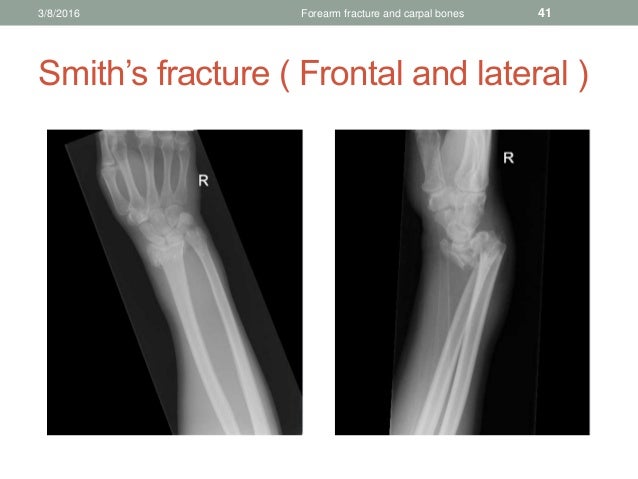

The traditional view is that this injury is most commonly caused by falling onto the back of the hand, but some. In this injury, there is displacement of the bone such that the wrist joint rests in front of its normal anatomic position.

It is useful to note that it is the head of the non-fractured bone that is dislocated. DISTAL RADIUS FRACTURES Colles Fracture VS Smith Fracture t.me/MedNoteCollection - medicine medicalstudent doctor mednotecollection orthopedic. About Press Copyright Contact us Creators Advertise Developers Terms Privacy Policy & Safety How YouTube works Test new features NFL Sunday Ticket Press Copyright. Nondisplaced or minimally displaced fractures of the distal wrist, such as Colles and Smith fractures or greenstick, buckle, and physeal fractures in children carpal bone fractures other than. Wrist fracture in which the distal end of the radius is displaced forwards. The Smith’s fracture is a specific type of injury to the forearm bone (the radius) near the wrist joint.